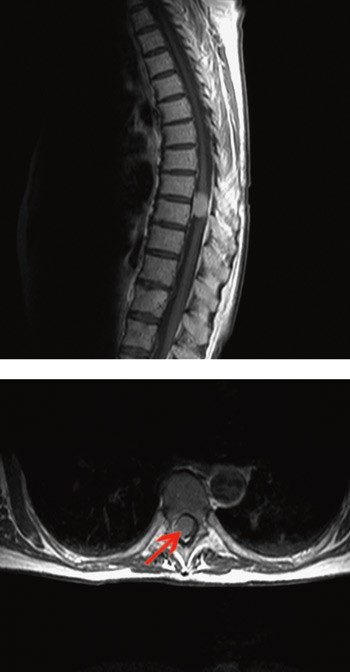

27 svulster var intradurale, mens bare én var ekstradural og intraspinal. 21 av svulstene var torakale, fem cervikale, én lumbal og én sakral. I aksialplanet hadde 15 lateralt feste mot dura, sju ventralt og fem posteriort. Festepunktet mot dura for det ene ekstradurale intraspinale meningeomet kunne ikke fastslås (tab 1).

Som et indirekte mål på svulstenes kompresjon av de nevrale strukturene anslo vi svulststørrelsen som en prosentdel av spinalkanalens areal i det aksiale MR-snittet som viste maksimal masseeffekt av svulstene. Svulstene fylte i snitt 47 % (11 – 73 %) av spinalkanalen (tab 1).